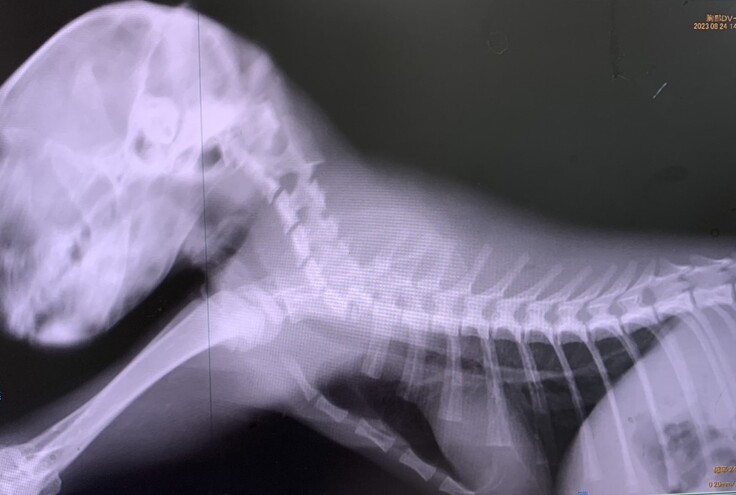

8月23日に保護された黒猫はクロッピーと名付けられました。糞尿で汚れ、背骨も肋骨も浮き出ていて体重は750グラム。起立どころか声を出す気力も無いほど弱っていました。収容翌日に当会から病院に搬送して検査をしてもらったところ、診断結果は第七頚椎骨折でした。寝たきりも頭をよぎりましたが、わずかに動く前脚と反応が残っている後脚、尻尾にささやかな希望を持って治療とリハビリを始めました。